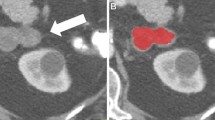

On adrenal glands, benign tumours generally change the hormone equilibrium, and malign tumours usually tend to spread to the nearby tissues and to the organs of the immune system. These features can give a trace about the type of adrenal tumours; however, they cannot be observed all the time. Different tumour types can be confused in terms of having a similar shape, size and intensity features on scans. To support the evaluation process, biopsy process is applied that includes injury and complication risks. In this study, we handle the binary characterisation of adrenal tumours by using dynamic computed tomography images. Concerning this, the usage of one more imaging modalities and biopsy process is wanted to be excluded. The used dataset consists of 8 subtypes of adrenal tumours, and it seemed as the worst-case scenario in which all handicaps are available against tumour classification. Histogram, grey level co-occurrence matrix and wavelet-based features are investigated to reveal the most effective one on the identification of adrenal tumours. Binary classification is proposed utilising four-promising algorithms that have proven oneself on the task of binary-medical pattern classification. For this purpose, optimised neural networks are examined using six dataset inspired by the aforementioned features, and an efficient framework is offered before the use of a biopsy. Accuracy, sensitivity, specificity, and AUC are used to evaluate the performance of classifiers. Consequently, malign/benign characterisation is performed by proposed framework, with success rates of 80.7%, 75%, 82.22% and 78.61% for the metrics, respectively.

• Different types of adrenal tumours can include similar features (i.e., intensity, size, shape), while same-kind tumours can involve different features.

• Related to handicaps, a framework including robust feature extraction and classification methods is needed to categorize adrenal tumours.